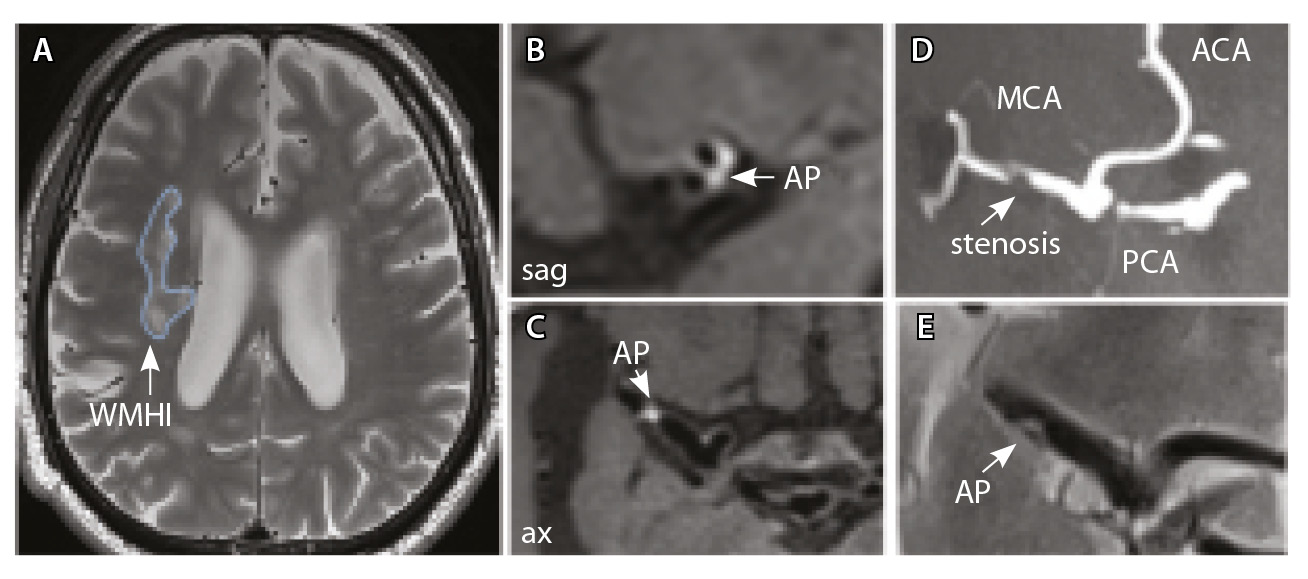

Рис. 3. Пациент Ц., 53 года, с признаками церебральной микроангиопатии (F3 по шкале Fazekas), атеросклерозом интракраниальных артерий, без формирования гемодинамически значимых стенозов. А – магнитно-резонансная томография (МРТ) головного мозга, режим Т2-взвешенного изображения: видны обширные сливные зоны гиперинтенсивности белого вещества (ГИБВ) с наличием на этом фоне лакунарных инфарктов; Б, В, Г – МРТ сосудистой стенки, режим T1-TSE-db-FS после контрастного усиления: в сегменте М1 левой средней мозговой артерии (СМА) визуализируется эксцентричная атеросклеротическая бляшка (АСБ), интенсивно накапливающая контрастный препарат; Д – трехмерная магнитно-резонансная времяпролетная (3D ToF) ангиография: выявляется неровность контуров левой СМА в сегменте М1; ax – аксиальная, sag – сагиттальная, cor – коронарная плоскости; ВСА – внутренняя сонная артерия; ПМА – передняя мозговая артерия

Рис. 4. Пациент К., 69 лет, с признаками церебральной микроангиопатии (F2 по шкале Fazekas) и атеросклерозом интракраниальных артерий, с формированием гемодинамически значимого стеноза в сегменте М1 правой средней мозговой артерии (СМА): А – магнитно-резонансная томография (МРТ), режим Т2-взвешенного изображения: видны множественные сливные очаги гиперинтенсивности белого вещества (ГИБВ); Б, В – МРТ сосудистой стенки, режим T1-TSE-db-FS после контрастного усиления: в сегменте М1 правой СМА визуализируется эксцентричная атеросклеротическая бляшка (АСБ), интенсивно накапливающая контрастный препарат; Г – трехмерная магнитно-резонансная времяпролетная (3D ToF) ангиография: виден стеноз правой СМА в сегменте М1; Д – режим HR Т2-TSE: видна АСБ в сегменте М1 правой СМА; ax – аксиальная, sag – сагиттальная плоскости; ЗМА – задняя мозговая артерия; ПМА – передняя мозговая артерия